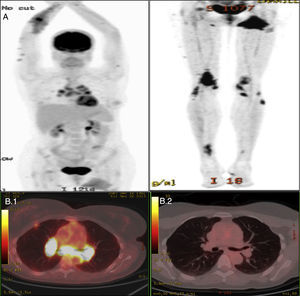

| Pruebas complementarias | ECA > 100 (VN 8-52mg/dl).PET: afectación cutánea, adenopática mediastínica, pulmonar, ósea y muscular (fig. 1) | ECA>100mg/dlPET: afectación adenopática mediastínica, pulmonar y ósea | ECA>100mg/dlTC: afectación pulmonar y adenopática |

Estudio de medicina nuclear del caso 1. A) Estudio gammagráfico con proceso inflamatorio activo que afecta a las extremidades superiores e inferiores, ganglios mediastínicos, parénquima pulmonar, hueso y músculo del glúteo izquierdo. B.1) Estudio PET con afectación ganglionar mediastínica antes del tratamiento. B.2) Estudio PET después del tratamiento.